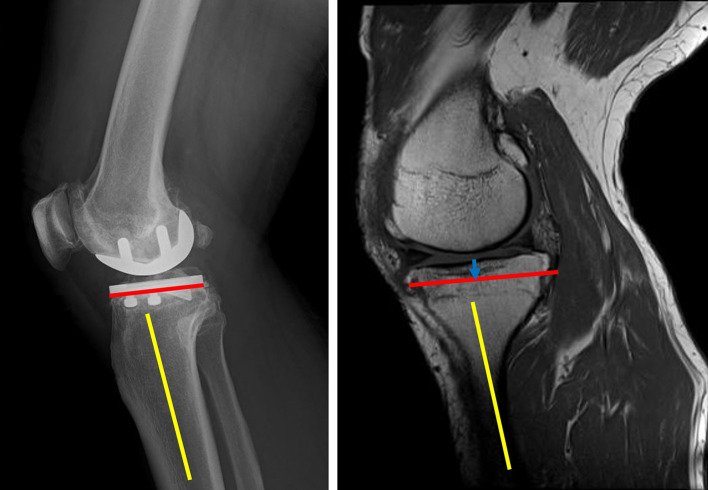

Methods: Preoperative MRI and postoperative radiographs obtained from 50 patients with unicompartmental KOA who underwent fixed-bearing UKA were analyzed. The amount of tibial resection was determined from the surgical records, and a line was drawn parallel to the tibial posterior tilt angle on the sagittal MR image to create a virtual tibial cut line. The tibial resection width measured from the anteroposterior image of the postoperative radiograph was projected onto the transverse plane containing the intersection between the virtual tibial cut line and the posterior tibial cortex, after which a line was drawn parallel to the medial or lateral intercondylar ridge. We then determined whether the PA was within an extension of the osteotomy area. The shortest distance (Distance 1) between the posterior tibial cortex and the PA within the osteotomy area was measured. In addition, the shortest distance between the line extending the osteotomy posteriorly and the PA was measured (Distance 2).

Results: The medial UKA (group M) and lateral UKA (group L) group comprised 41 and 9 cases. The percentage of PA located behind the osteotomy plane was significantly higher in group L than in group M [6/9 knees (66.7%) vs. 2/41 knees (4.9%); P < 0.001]. The distance 1 was 12.6 (4.3) mm in group M and 7.9 (3.7) mm in group L (P = 0.004). The distance2 was 11.1 (4.9) mm in group M and 2.6 (3.5) mm in group L (P < 0.001).

Conclusion: During lateral UKA, the PA was often located behind the tibial osteotomy plane and close to the posterior tibial cortex. Nearly 5% of medial UKAs, the artery was located behind the osteotomy plane.